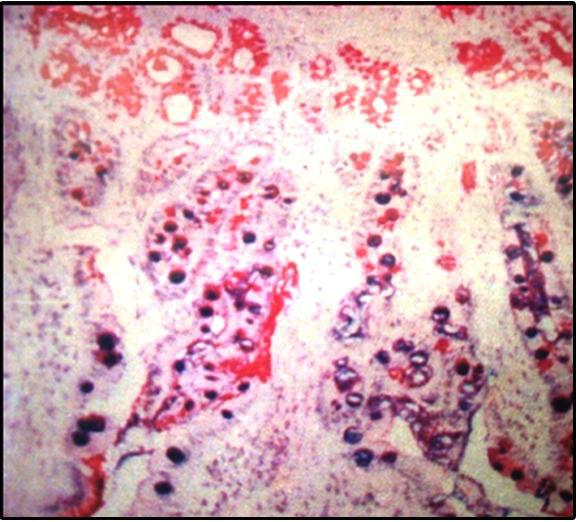

Fig. 11: Histopathological examination showing the gastric mucosa of rat suffering from moderate infection Fig. 12: Histopathological examination showing the gastric mucosa of rat suffering from mild infection Fig. 13: Histopathological examination showing the gastric mucosa of rat free from H. pylori infection

From the histopathological examination it is obvious that group of rats receiving plain drugs solution at dose amoxicillin trihydrate 30 mg/Kg, metronidazole 15 mg/Kg and famotidine 0.45 mg/Kg, showed moderate infection with a large population of H. pylori shown in fig. 11. Group of rats receiving CH film formulation at same doses showed mild infection with a large population of H. pylori Shown in fig. 12. Group of rats receiving CH-PAA IPC film formulation at same dose showed total absence of H. pylori infection shown in fig. 13, From the histopathological examination it is obvious that groups receiving drugs in the form of CH-PAA IPC film and CH film formulation at doses amoxicillin trihydrate 30 mg/Kg, metronidazole 15 mg/Kg and famotidine 0.45 mg/Kg were better than the corresponding solution form at same doses, to eradicate the H. pylori infection.